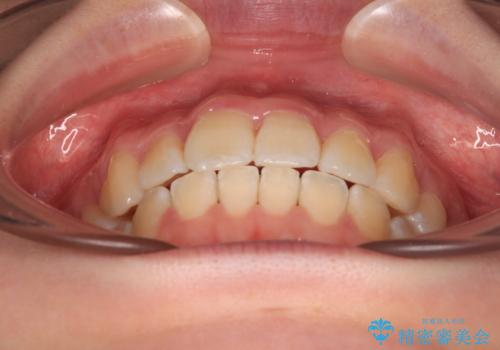

【モニター】八重歯を片側の抜歯矯正で治す メタルブラケット装置

- 八重歯とずれた正中を気にして来院された患者様です。

非抜歯矯正ではデコボコを解消することでより口元が突出する可能性があるため、上顎右右側の小臼歯1本の抜歯を行い、ワイヤー装置による矯正治療を行うこととしました。

正中位置を合わせるために、上顎臼歯部にアンカースクリューを埋入することとしました。

お仕事の予定を調整しやすく、平日の昼の時間帯に通院可能であったので、非常にスムーズに治療を進めることができ、1年半で無事に治療を終えることができました。